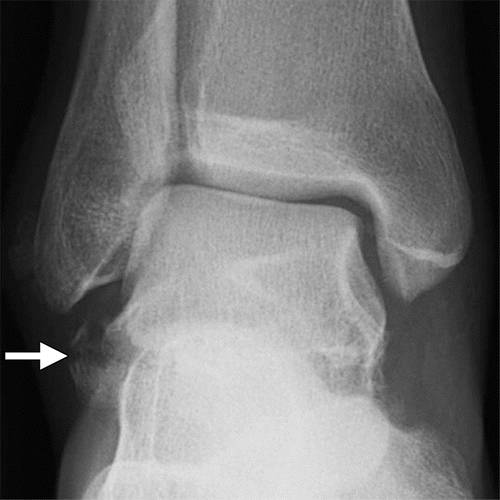

图11b外侧距骨软骨骨折。 (a)踝关节的AP射线照片显示外侧的距骨穹顶(箭头)的微妙的骨软骨骨折,被重叠的腓骨遮蔽。 (b)脚踝的斜位视图更好地显示骨折(箭头)。

图12a内侧踝关节骨软骨骨折。 AP(a)和斜位(b)踝骨的X线照片显示椎间融合器的移位骨软骨骨折(黑色箭头)。 还注意到倾斜的骨干腓骨骨折(箭头),syndesmotic加宽(双头箭头)和内侧清晰空间加宽(白色箭头b),符合syndesmotic和三角肌韧带复杂损伤的存在。